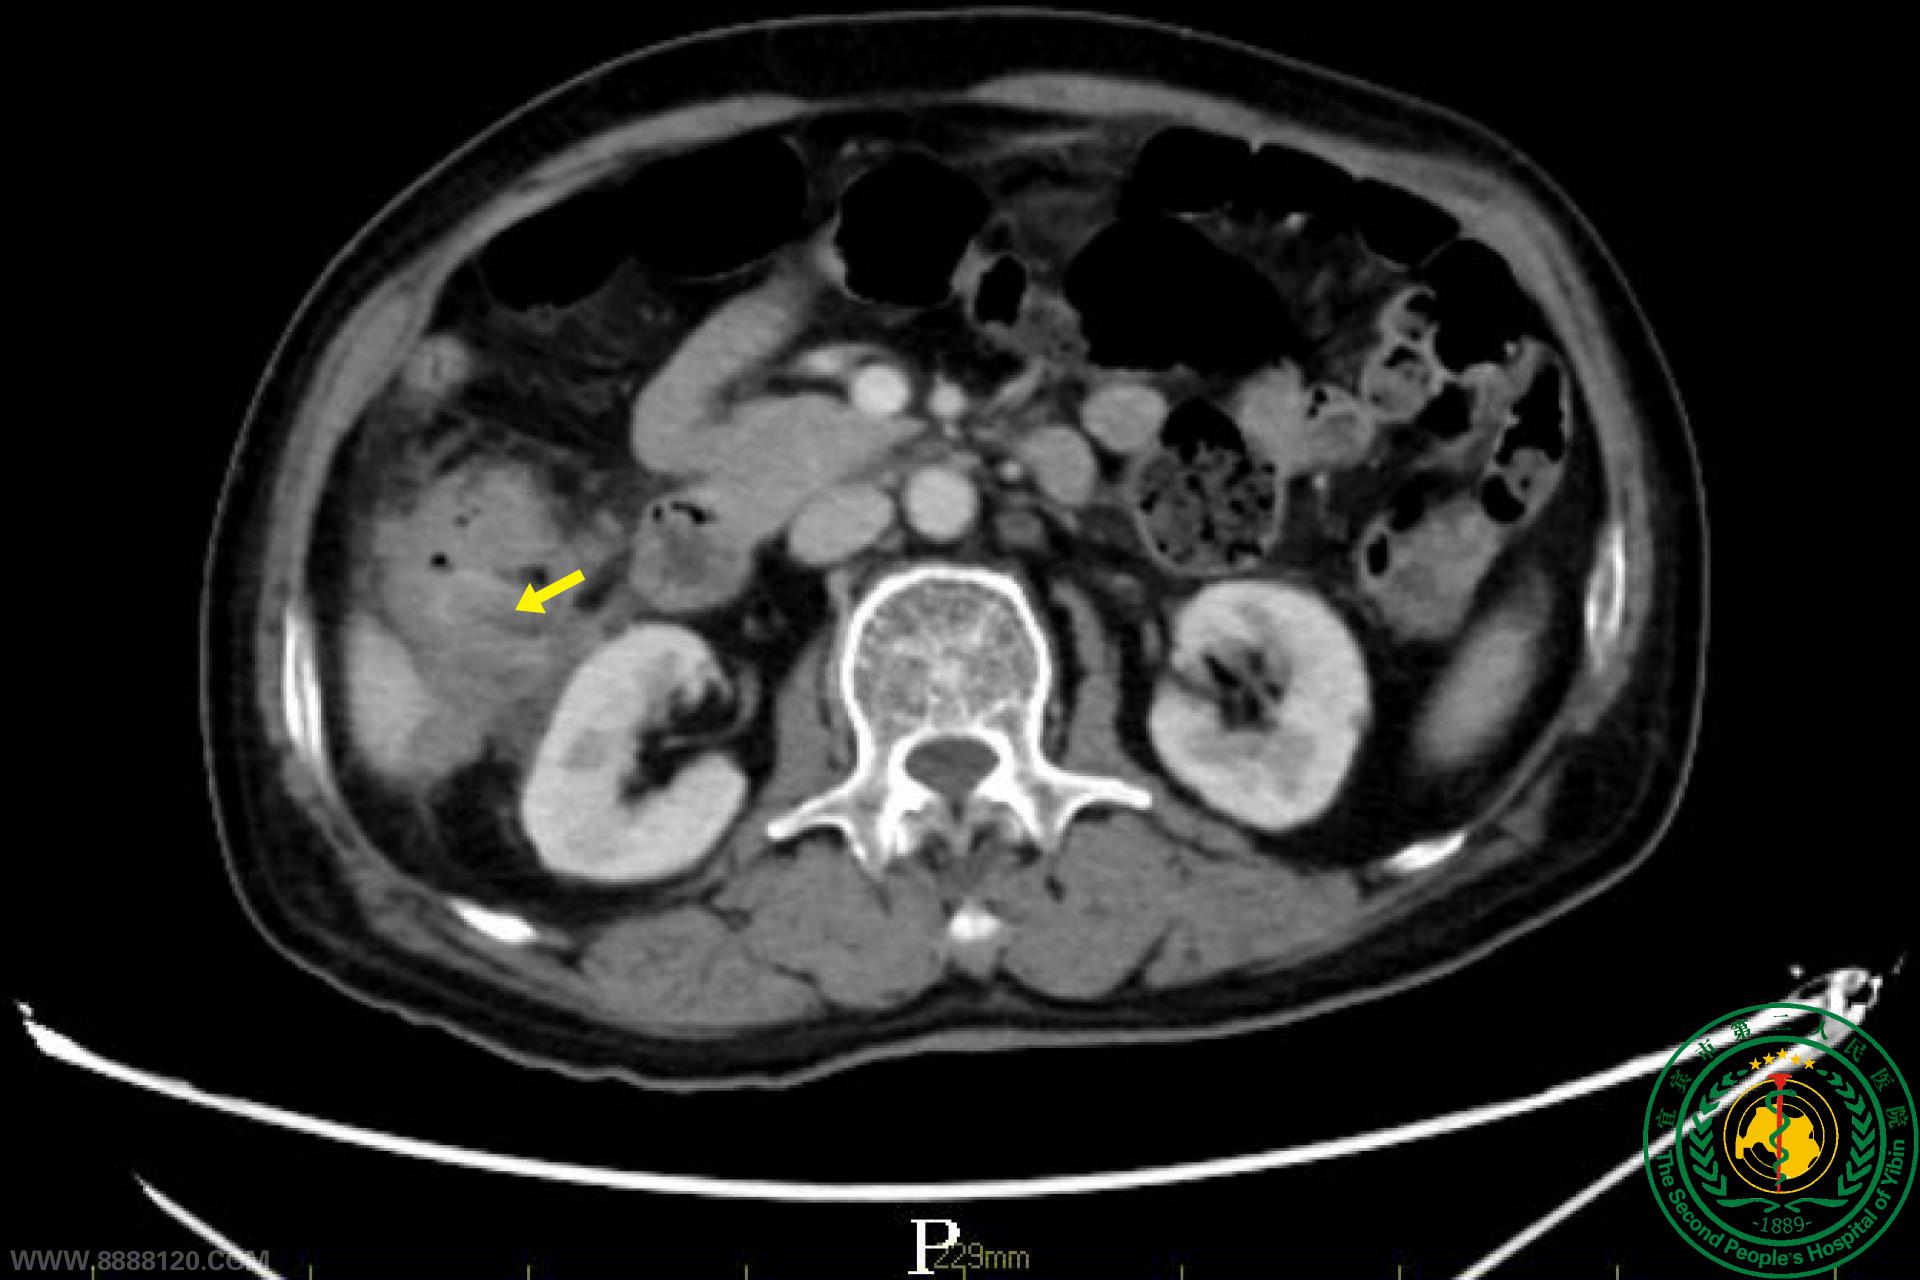

宜宾二院多学科助力,为七旬老人切除巨大肠癌

宜宾二院多学科助力,为七旬老人切除巨大肠癌51745